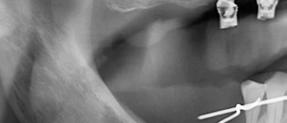

Protocolo Di2gitalArch® 2.0: Carga inmediata en el día en maxilar superior atrófico. Con Ziacom Galaxy, por el Dr. Luis Cuadrado Canals.